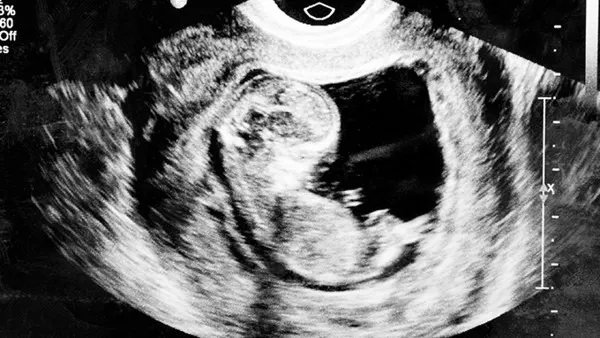

每一个女性在怀孕期间的时候,都需要进行很多次的检查,B超检查就是最为常见的一种,它可以观测到胎儿在母体当中的基本情况,就像检查时很多女性都会发现有子宫前位的情况。

这种情况下,经常通过B超检查可以发现,部分胎盘会覆盖在女性的宫颈内口的位置。

这种情况下通过B超能够发现胎盘位于子宫的下半部分,胎盘的下部分会靠近宫颈内口的边缘位置。